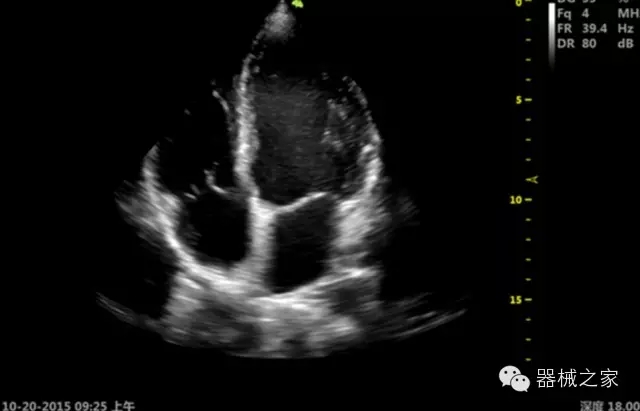

臨床圖片賞析

·心功能綜合指數(shù)(TEI指數(shù)):用于左、右心室整體心臟收縮舒張功能評估的測量方法;

·全方位可調(diào)M型:有利于更好的觀察心腔大小及室壁階段性運(yùn)動(dòng)的異常情況;

·組織多普勒成像(TDI):TDI可定量評價(jià)心肌運(yùn)動(dòng),判斷是否有局部病變,還可評價(jià)早期的舒張功能;